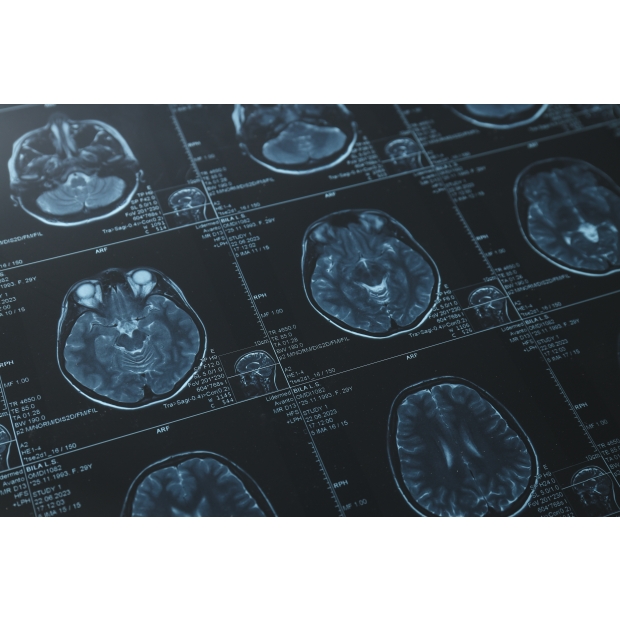

利用獨創之AI技術針對多類型腦腫瘤(聽神經瘤、腦膜瘤、以及腦轉移瘤)進行術前磁振造影腦瘤自動圈註,給予客觀且準確的腦瘤體積定量分析。

• DeepBT Detector擁有人工智慧腦瘤輔助偵測模組和符合DICOM標準的影像瀏覽介面(Viewer),提供T1加權對比度增強磁振造影(T1W+C)T2加權磁振造影(T2W)等影像解析度,並自動判讀出病灶輪廓。